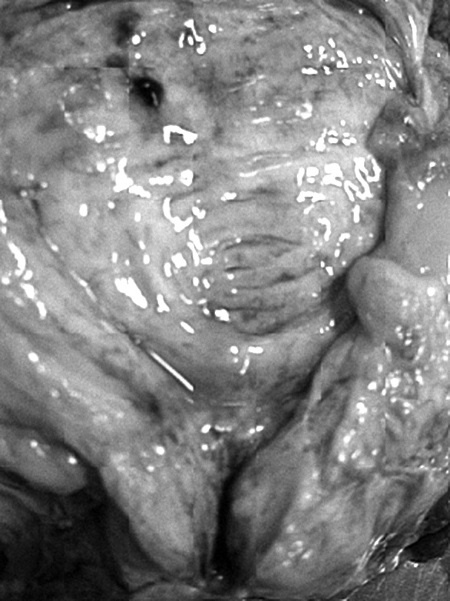

Рис. 1. Результаты аутопсии больного 68 лет

Доброкачественная гиперплазия предстательной железы